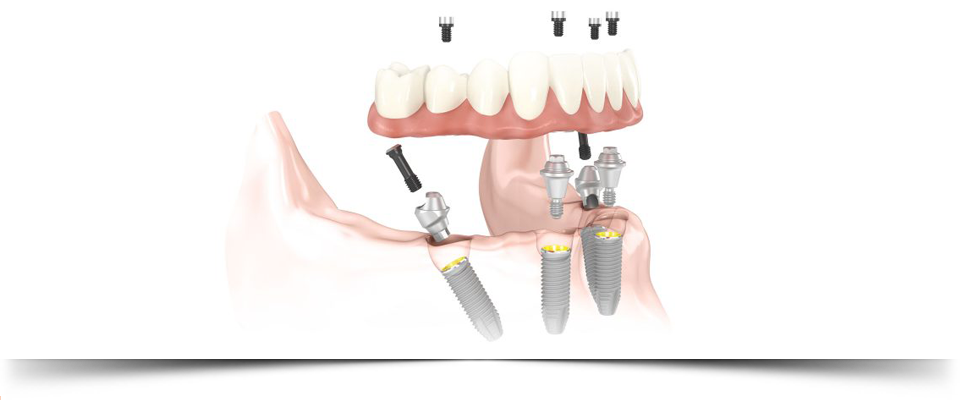

LOS IMPLANTES son la solución ideal para la sustitución de dientes perdidos, ya se trate de una pérdida parcial o completa de ellos. A veces es necesario realizar algún tipo de cirugía previa para su posterior colocación, como la elevación de seno o el ingerto óseo.